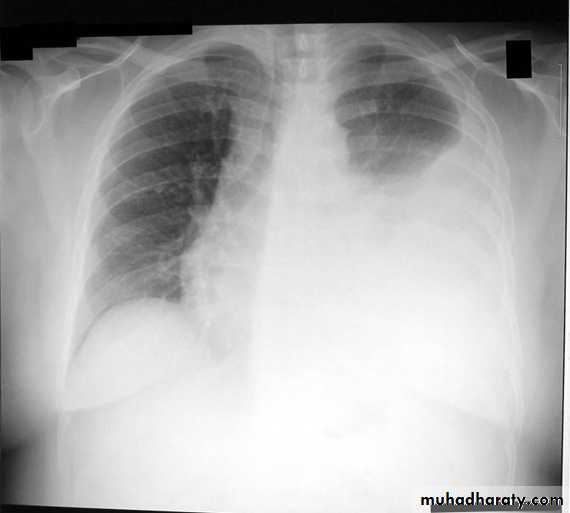

Chest X ray: The pleural fluid accumulates in the most dependent part of the thoracic cavity

The normally sharp posterior costophrenic angle is obliterated.

Upper surface is meniscus-shaped (meniscus sign).

Around 200 mL of fluid is required in order for it to be detectable

on a PA chest X-ray

The amount of pleural effusion may be small, large or massive.